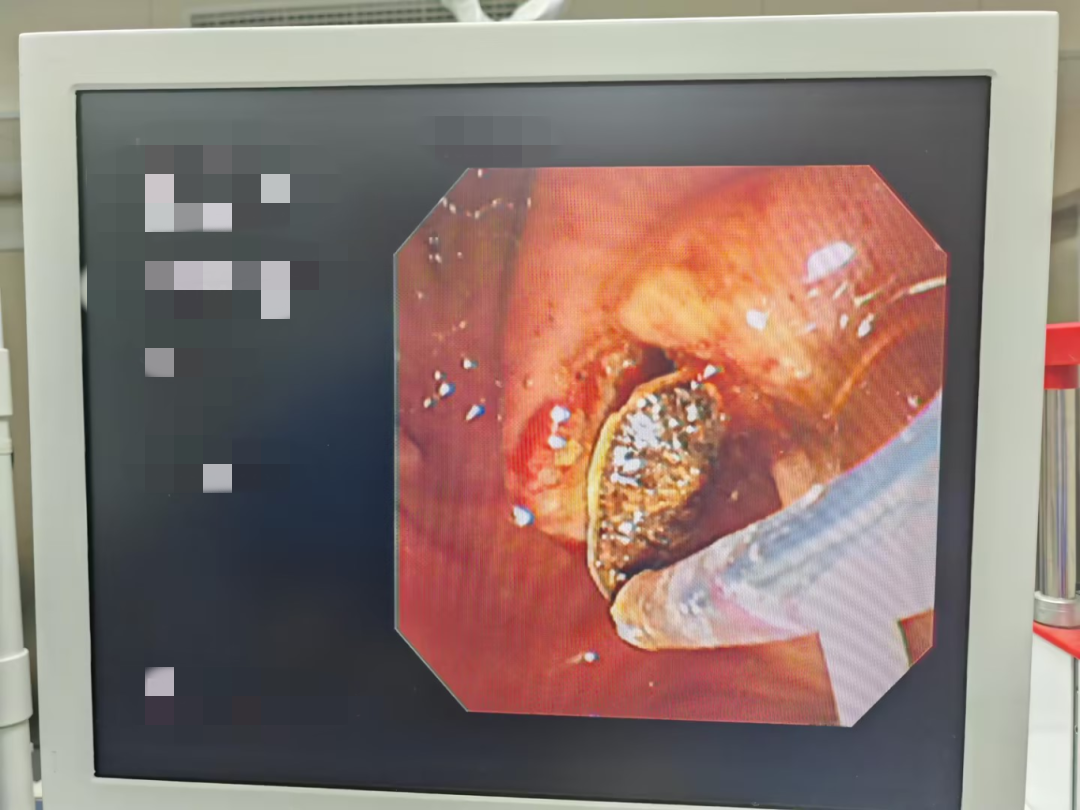

5日后,唐大爷的感染症状得到完全控制,决定开展二次手术,通过ERCP明确胆道病变情况,然后利用球囊扩张术扩大胆道开口,再根据结石的具体情况选择网篮碎石术、网篮取石术或球囊取石术将结石取出。最后通过ENBD(内镜下鼻胆管引流术)进行胆汁引流,确保胆道通畅,防止并发症的发生。